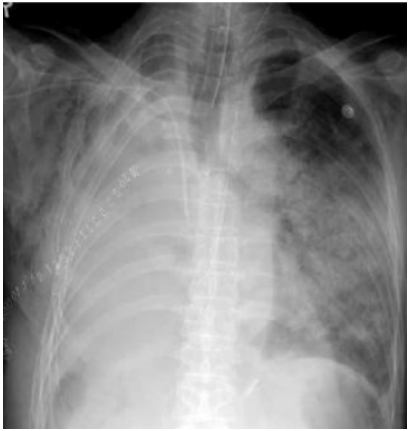

VAP的影像学标准缺乏特异性,例如胸部X线片显示两肺上叶斑片状高密度影,可能是感染,也可能是其他非感染性疾病,如血管炎、嗜酸细胞性肺炎、过敏性肺炎、肉瘤样变、血管炎等。

下图是68岁老年男性患者,因多重耐药结核菌感染行右肺切除,切除后第2日胸部X线片改变,双肺大片实变,最终证实是肺水肿、ARDS。